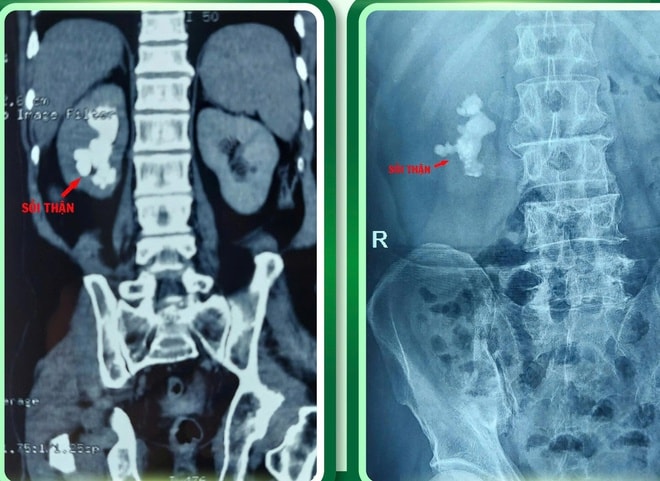

Bệnh nhân là ông Nguyễn Bá H. (51 tuổi, trú xã Quỳ Hợp, Nghệ An), nhập viện trong tình trạng thể trạng suy kiệt, mắc sỏi san hô thận phải kích thước lớn kèm xơ gan. Đây là nhóm bệnh nhân có nguy cơ chảy máu rất cao, mọi can thiệp phẫu thuật đều tiềm ẩn rủi ro đe dọa tính mạng.

Sau hội chẩn toàn diện, ê-kíp Khoa Ngoại tổng hợp đã thống nhất lựa chọn phẫu thuật nội soi lấy sỏi thận qua da (Mini PCNL) – phương pháp ít xâm lấn, giảm tổn thương nhu mô thận và hạn chế tối đa nguy cơ chảy máu.

Ca mổ diễn ra an toàn, kiểm soát tốt mất máu, toàn bộ sỏi san hô được lấy sạch. Hiện sức khỏe bệnh nhân phục hồi tích cực, ăn uống, đi lại bình thường và dự kiến xuất viện trong vài ngày tới.